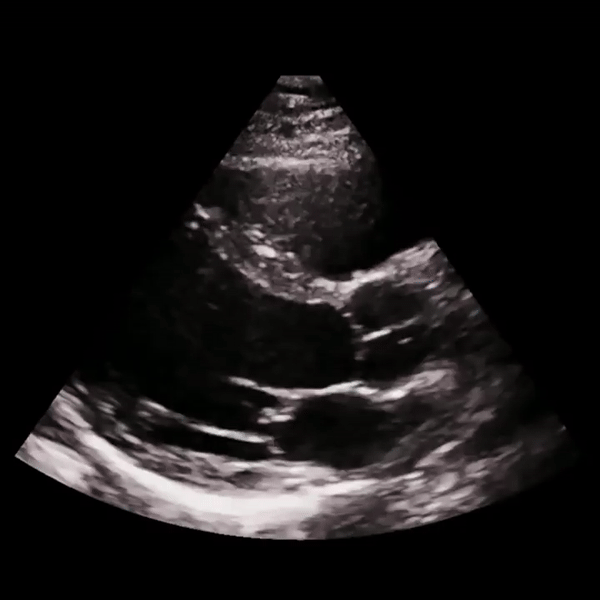

We partnered with a leading biotech company to revolutionize their echocardiogram analysis process using advanced computer vision technology. Our solution automatically labels, classifies, and grades echocardiograms in a fraction of the time significantly reducing manual workload and enhancing diagnostic precision.

5,000,000+

99+%

Frames processed

Accuracy